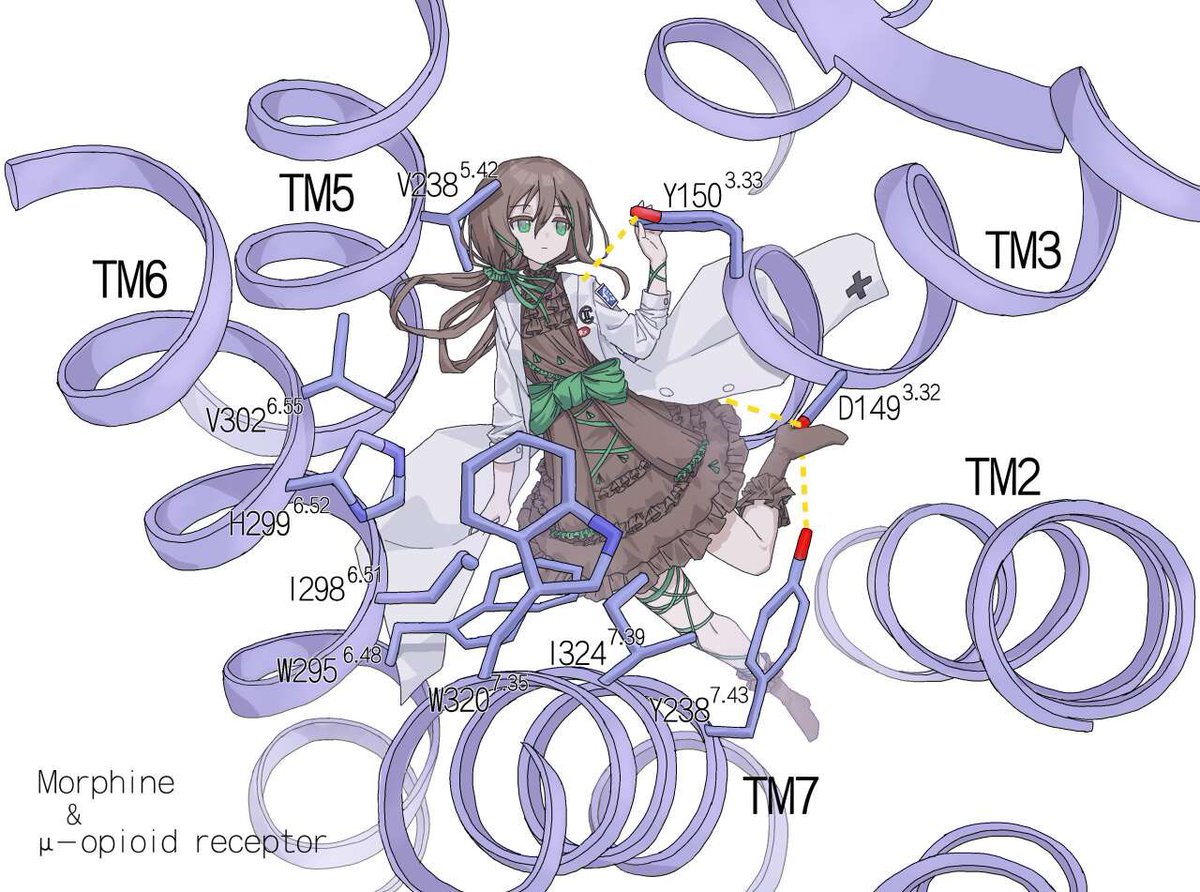

首先,从定义上讲,“反解离(anti-dissociative)”并不是一个标准的医学术语或者广泛认同的药理学分类。在正规资料,比如医学文献、维基百科、精神药理学教科书中,目前并没有“反解离药物”这个正式概念。

看上去像是为了描述某类特定效应而创造的术语(可能是nmda受体活性增强),用来对抗因NMDA受体拮抗剂(比如氯胺酮、DXM、PCP等)引发的解离体验(dissociation)。

那么更常见的是将其归入认知增强剂(cognitive enhancers),特别是改善认知连接性(connectivity)和现实感知(reality testing)的类型。

但其实在药理学上,单纯用“受体激动剂”来逆转“受体拮抗剂”的效应,有时会导致过度激活。

对于NMDA受体而言,过强的NMDA活化本身就与兴奋性毒性(excitotoxicity)和精神病样症状(psychotomimetic effects)有关,比如谷氨酸风暴可以引发严重的焦虑、妄想、乃至癫痫。

也就是说,简单地“激动-解除拮抗”在中枢神经系统是很危险的做法,尤其是对于易感个体(如有精神分裂素质的人)。

科学的处理方式一般是通过更细致的调节,比如微调NMDA/AMPA平衡、调节其他辅助途径(如GABA、5-HT、mGluR受体),而不是简单粗暴地用“NMDA增强剂”去顶回去。

而临床处理药物中毒中,其实医生更常用的做法是保守、支持性的治疗,比如补液,促进代谢,必要时镇静,以及监测生命体征防治并发症。

药物拮抗与受体激动之间,往往牵扯到的是复杂的适应性变化(receptor upregulation/downregulation),

不是简单的“给多一点刺激就能抵消”的关系